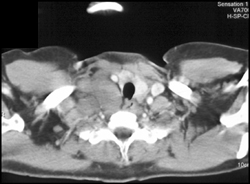

Plastic Bronchitis With Mucus Plug in Right Mainstem Bronchus